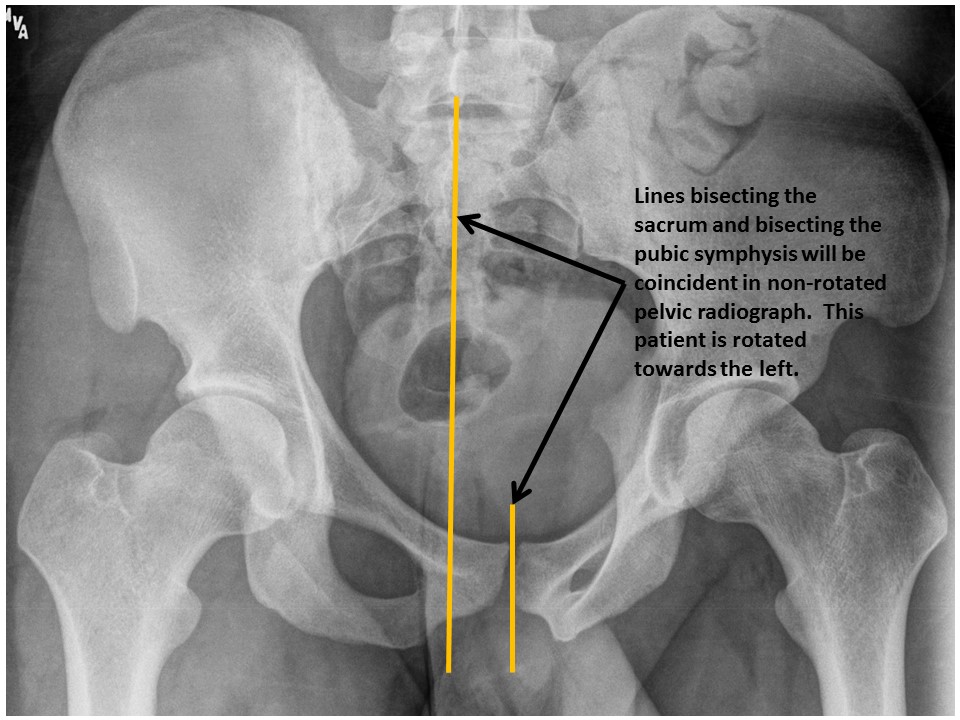

The image is rotated. [Yes/No]